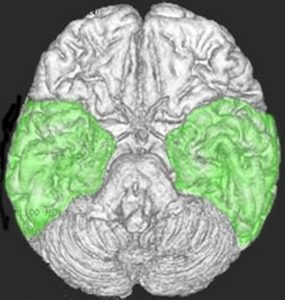

側頭葉の解剖図

側頭葉の解剖図です

側頭葉の解剖図です。表面からは見えませんが,深部の海馬というところには記憶の中枢があります。左側頭葉には言語の中枢もあります。聴覚や味覚,情動などの中枢も側頭葉にあります。

脳の底面(左)と正面(右)から